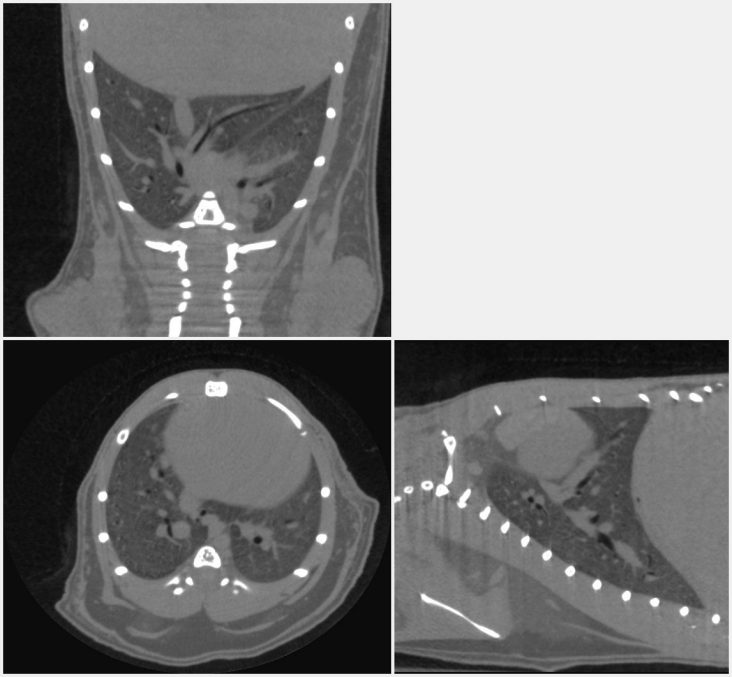

5. Orthogonal cross-sections through the mouse lung scannedin vivo, showing the blood vessels and large airways inside the lung.